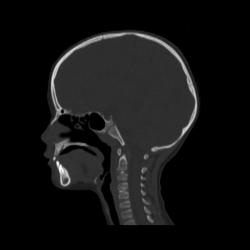

Ребенок 6 лет. Жалобы на выраженные боли в шейном отделе позвоночника. Со слов матери, боли в шее беспокоили длительное время. 2 недели отмечалась незначительная травма - девочка резко повернула голову в сторону, боли в шее услились. В настоящий момент  отмечаются выраженные боли в шее, резкое ограничение движений, повышение температуры тела, воспалительные изменения в анализах, (возможно, связанные с пиелонефритом, который также имеет место). Поступала с направительным диагнозом "ротационный подвывих атланта", однако данные рентгенографии заставили расширить круг диагностического поиска.Родовую травму мать отрицает. Хотелось бы узнать мнение уважаемых коллег.

Уважаемая коллега! С точки зрения классической рентгенологии (с учётом качества представленных снимков) могу высказать следующее:

- определяется выраженный антелистез тела С5;

- двуконтурность тел С3 и С5 может свидетельствовать о нарушении целостности костной ткани указанных тел позвонков;

- безусловно, межпозвонковые диски "поехали".

Вижу ещё раздвоенный axis.

Аксис не раздвоен, это нормальная картина для шести лет, просто верхушка зуба еще хрящевая.

Спасибо. Буду знать. По заданной теме: не хотелось бы быть освистанным, но смею предположить ювенильный ревматоидный артрит.

Случай помню. Закончилось все на удивление просто - после недели вытяжения петлей Глиссона боли ушли, движения в ШОП восстановились в полном объёме. Рентгенологические данные расценили как врожденную аномалию развития. Воспалительные изменения в анализах - как проявления пиелонефрита. В любом случае, из нашего поля зрения ребёнок ушел к нефрологам.